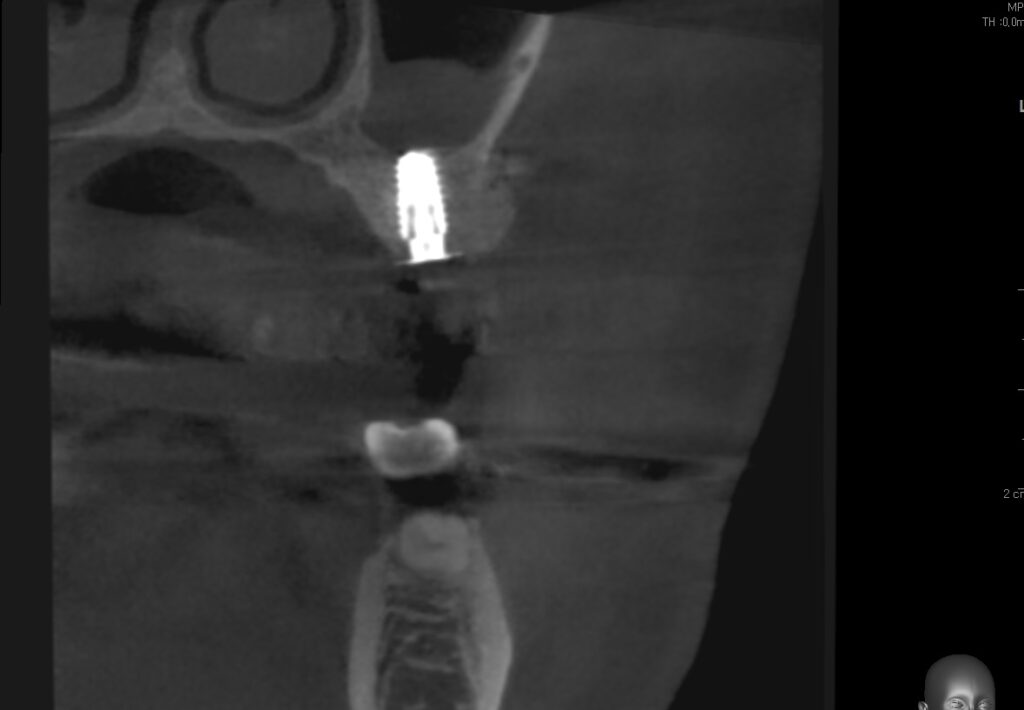

사진을 보면 무엇이 보이시나요

바로 임플란트가 파절이 일어났습니다

여기서 임플란트가 왜 파절이 일어났을까요

왜 임플란트가 파절 즉 부러졌을까요

여기에 대한 대답은 간단합니다

씹는 저작력에 비하여

임플란트의 사이즈를

얇은 사이즈 즉 작은 사이즈를 심어서 그런것입니다

대구치 사람이 저작하는 가장 큰 힘을 받는

최후방 치아의 경우

임플란트의 직경 최소 4.5mm이상의 임플란트

식립이 지켜야 하는 원칙입니다

하지만 이 환자분은 4.0 직경의 임플란트가 식립이 되었는데요

그렇다면 여기서 궁금한점은

왜 4.0직경의 얇은 임플란트를 심었을까요?

그 이유는 치조골 직경이 얇은

부분에 치조골 이식없이

얇은 임플란트를 심었기 때문입니다